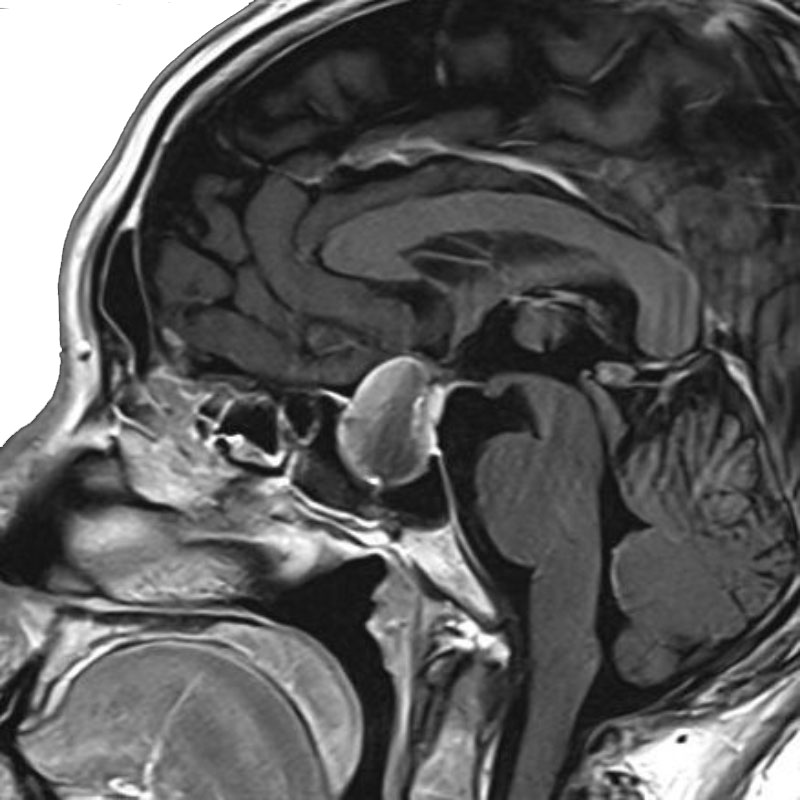

脳動脈瘤(Acom)

クリッピング術

松田/濵田/元永